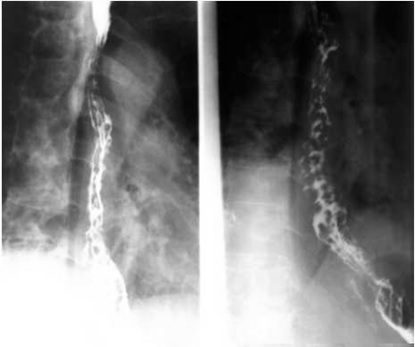

05卷-5.男性,胸骨后隐痛一年,请选择正确答案(本题满分2.00分)

本题答案:B

题目解析:【该题针对“造影-食管静脉曲张”知识点进行考核】